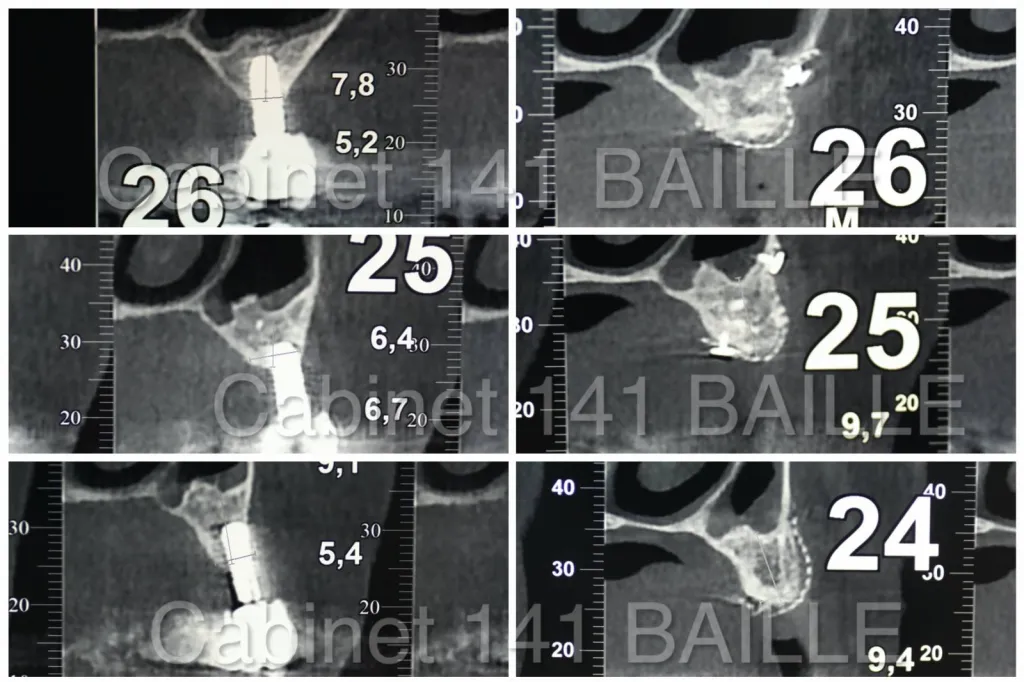

Le chirurgien  spécialisé en implantologie va pouvoir placer des coffrages osseux qui seront préformés sur une réplique 3D du crâne du patient issu de l'analyse radiologique "cone-beam "  (Scanner).

Ces coffrages en grilles titane , vont permettre à l'os de se régénérer avec une protection mécanique (grille titane) et isolé par une membrane de ROG de type Bioigide®.